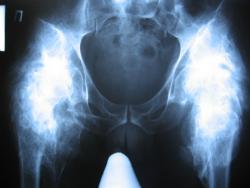

Последствия ПСМТ(04.08.04). Спастический грубый тетрапарез до плегии слева. Массивные гетеротопические оссификаты обоих тазобедренных сусвтавов, в следствии нейро-трофических нарушений. До травмы пациент был абсолютно здоров.

Наверное, это можно назвать нейрогенной остеоартропатией. Красивая картинка.